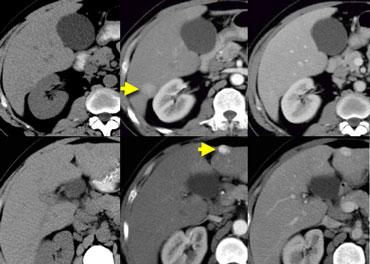

NECT, arterial and portal venous phase in a patient with Hepatitis C with two lesions in the liver (arrows).

Trong thì động mạch, chúng ta thấy hai tổn thương tăng sinh mạch.

Các hình ảnh phía trên cho thấy một tổn thương đồng tỷ trọng với gan trên CCLVT không tiêm thuốc.

Trong thì động mạch có sự ngấm thuốc, nhưng không đậm bằng tỷ trọng máu trong lòng mạch.

Trong thì tĩnh mạch cửa, tổn thương lại đồng tỷ trọng với nhu mô gan xung quanh và không thể nhìn thấy.

Nếu chỉ có thì tĩnh mạch cửa, chắc chắn bạn sẽ bỏ sót tổn thương này.

Các hình ảnh phía dưới cho thấy một tổn thương có thể nhìn thấy trên tất cả các hình ảnh.

Bạn thấy nó trên CCLVT không tiêm thuốc và có thể nhận xét rằng nó giảm tỷ trọng so với gan.

Tuy nhiên, nếu nhìn vào tỷ trọng máu trong lòng mạch, bạn sẽ nhận thấy rằng ở tất cả các thì, tổn thương có tỷ trọng tương đương với máu trong lòng mạch.

Vậy chúng ta có một ung thư biểu mô tế bào gan ở thùy phải trên các hình ảnh phía trên và một u máu ở thùy trái trên các hình ảnh phía dưới.

Điều quan trọng là phải xem xét tất cả các thì chụp.